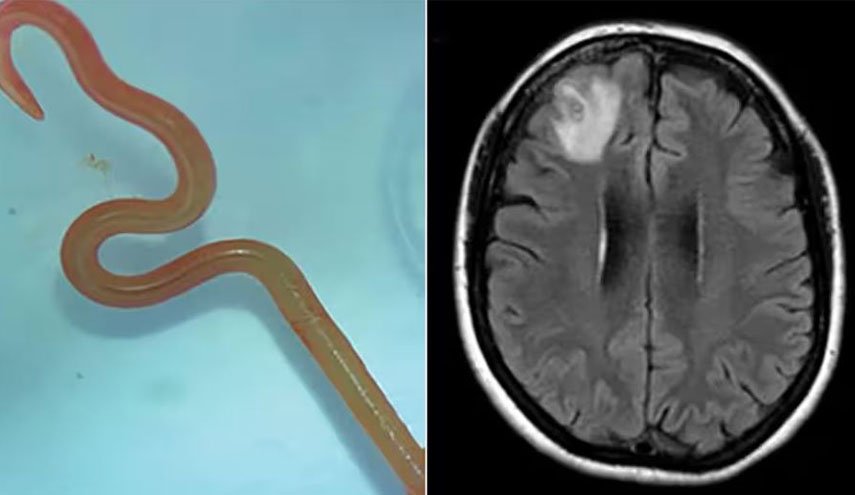

جراحة الأعصاب بيتسي غرونش أوضحت بعض أسباب هذا الداء وأعراضه لموقع "بز فييد" حيث قالت إن "ديدان الدماغ" هي طفيليات تصيب أجزاء من أجسامن.

وأضافت: "الأكثر شيوعًا دودة شريط لحم الخنزير، تينيا سوليوم (أو داء الكيسات العصبية)".

بحسب بيتسي فإن هذه الدودة لا يمكنها الانتقال إلى الدماغ لكن يرقاتها يمكنها ذلك، حيث تضع الدودة يرقاتها بمجرد دخولها للأمعاء مستخدمة أجسامنا كوسيط، وإذا لم يتم طرد البيض من أجسامنا من خلال البراز، فقد تنمو إلى يرقات.

يمكن لهذه اليرقات أن تنتقل إلى أعضاء أخرى من خلال مجرى الدم، قد تنتقل هذه الديدان الشريطية أيضا من إنسان إلى آخر إذا كان لدى الشخص عادات غير صحية مثل عدم غسل يديه جيدًا بعد استراحة الحمام.

وتابعت: "قد يستغرق ظهور أعراض عدوى الدماغ شهورا إلى سنوات، حيث لا تظهر الأعراض عادة إلا بعد موت اليرقات، وعندما تظهر في الدماغ، تشمل الأعراض الغثيان والنوبات والصداع".